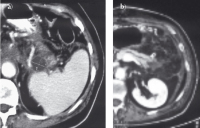

Abbildung 4: a) Der Leberabszeß mit Satellitenherden durchsetzt den linken Leberlappen (CT 8.8.2005). Die weiße Struktur entspricht dem über den Ductus Santorini in den Hauptpankreasgang eingelegten Stent. b) Präparat der linksseitigen Lobektomie vom 18.8.2005 mit eröffneten Leberabszessen.

Keywords: chronische PankreatitisFotoGastroenterologieLeberabszess